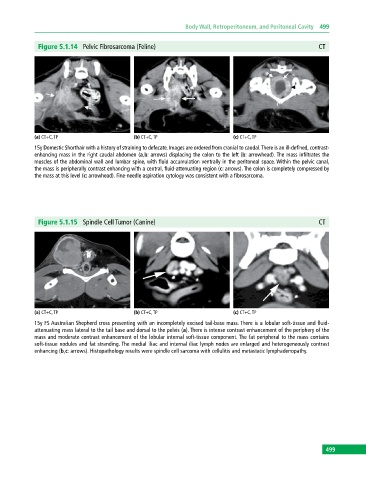

Figure 5.1.14 Pelvic Fibrosarcoma (Feline) CT

(a) CT+C, TP (b) CT+C, TP (c) CT+C, TP

15y Domestic Shorthair with a history of straining to defecate. Images are ordered from cranial to caudal. There is an ill‐defined, contrast‐

enhancing mass in the right caudal abdomen (a,b: arrows) displacing the colon to the left (b: arrowhead). The mass infiltrates the

muscles of the abdominal wall and lumbar spine, with fluid accumulation ventrally in the peritoneal space. Within the pelvic canal,

the mass is peripherally contrast enhancing with a central, fluid‐attenuating region (c: arrows). The colon is completely compressed by

the mass at this level (c: arrowhead). Fine‐needle aspiration cytology was consistent with a fibrosarcoma.

Figure 5.1.15 Spindle Cell Tumor (Canine) CT

15y FS Australian Shepherd cross presenting with an incompletely excised tail‐base mass. There is a lobular soft‐tissue and fluid‐

attenuating mass lateral to the tail base and dorsal to the pelvis (a). There is intense contrast enhancement of the periphery of the

mass and moderate contrast enhancement of the lobular internal soft‐tissue component. The fat peripheral to the mass contains

soft‐tissue nodules and fat stranding. The medial iliac and internal iliac lymph nodes are enlarged and heterogeneously contrast

enhancing (b,c: arrows). Histopathology results were spindle cell sarcoma with cellulitis and metastatic lymphadenopathy.